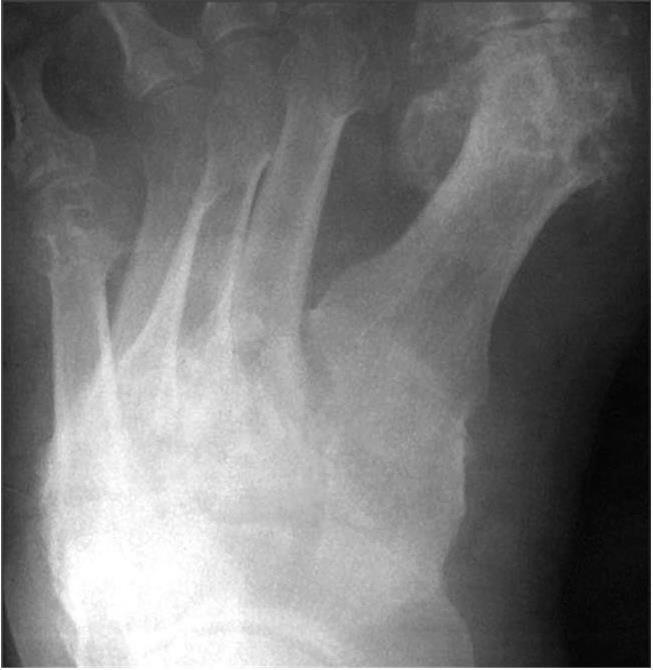

Множественные и крупные подагрические узелки наблюдают при резко выраженной гиперурикемии. Однако абсолютным признаком подагры может быть только выявление кристаллов мочевой кислоты. Кристаллы МУН (моноурата натрия) обнаруживают уже после первого эпизода артрита. Кристаллы МУН определяют в синовиальной жидкости даже вне приступа. Кристаллы уратов имеют вид палочек или тонких игл с обломанными или закругленными концами длиной около 10 мкм. Микрокристаллы уратов в синовиальной жидкости обнаруживают как свободно лежащими, так и в нейтрофилах. Рентгенологически вблизи тофусов выявляют округлую деструкцию костной ткани, обусловленную лизисом кости вокруг отложения кристаллов уратов (рис. 24, 25). Последние обычно рентгенонегативны, но иногда рядом можно выявить отложение солей кальция.

Рис. 24. Рентгенограмма костей запястья и лучезапястного сустава больной подагрой

Отчетливо видны множественные очаги деструкции округлой формы (симптом «пробойника»). Дефекты костной ткани преимущественно локализованы вне полостей суставов

Округлую костную деструкцию называют «штампованными дефектами», симптомом «пробойника». Деструкция обычно расположена субкортикально, как в эпифизах (субхондрально), так и на границе эпифиза и диафиза, а также может быть локализована вне сустава, в диафизах, с участками костной резорбции вокруг. При расположении уратов вблизи полости сустава из-за гибели хряща можно наблюдать сужение суставной щели. Как результат прорыва конгломерата уратов в полость сустава из кости может быть обнаружена краевая деструкция костной пластинки, но это наблюдают, как правило, на фоне других округлых очагов деструкции костной ткани — «пробойников». Рядом с отложением уратов можно видеть гипертрофическую костную реакцию. При значительной гибели суставного хряща подагра осложняется вторичным остеоартрозом с появлением краевых костных разрастаний — остеофитов.

В пожилом возрасте обнаружить подагрическую деструкцию можно не только в суставах стопы, коленных, локтевых, но и в мелких суставах и костях запястья. Подагрическое поражение костей и суставов запястья с множественными очагами деструкции, частичным анкилозированием при разрушении смежных отделов костей см. на рис. 24.